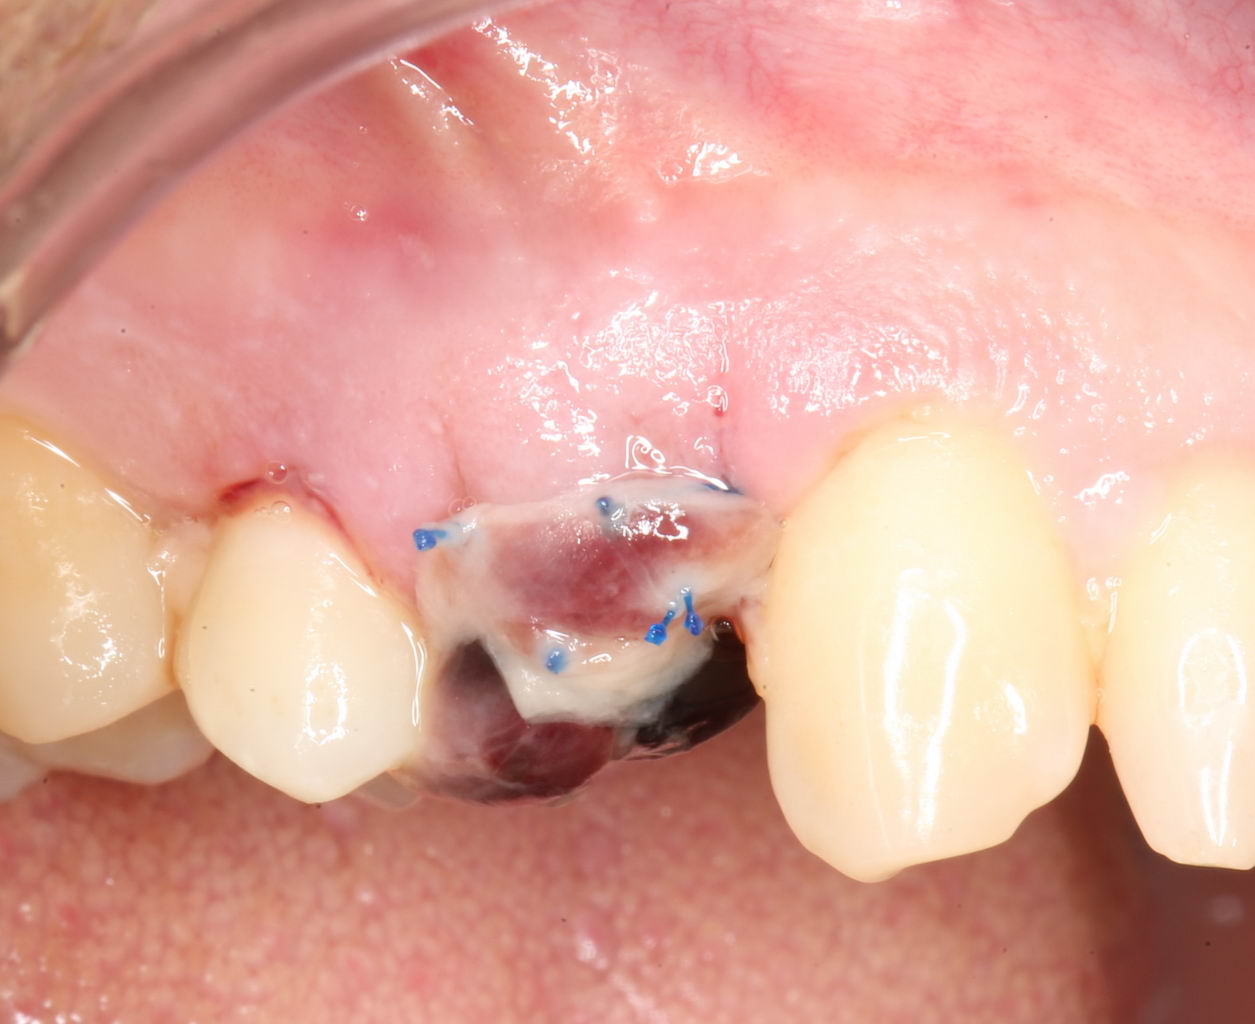

Послеоперационный период.

Как правило, послеоперационный период сопровождается рядом симптомов, главными из которых являются кровотечение и припухлость в области операции. К примеру, вот тот же пациент через два дня после операции:

Он полностью трудоспособен и не испытывает никакого дискомфорта. Отёков, как видите, тоже нет. Но было кровотечение. И это видно по состоянию послеоперационной раны:

На формирователе и швах повис большой кровяной сгусток. This is хорошо, поскольку он как защитная повязка, прикрывает рану от воздействия извне. Возможно, именно этим объясняется отсутствие каких-то неприятных симптомов в послеоперационном периоде.